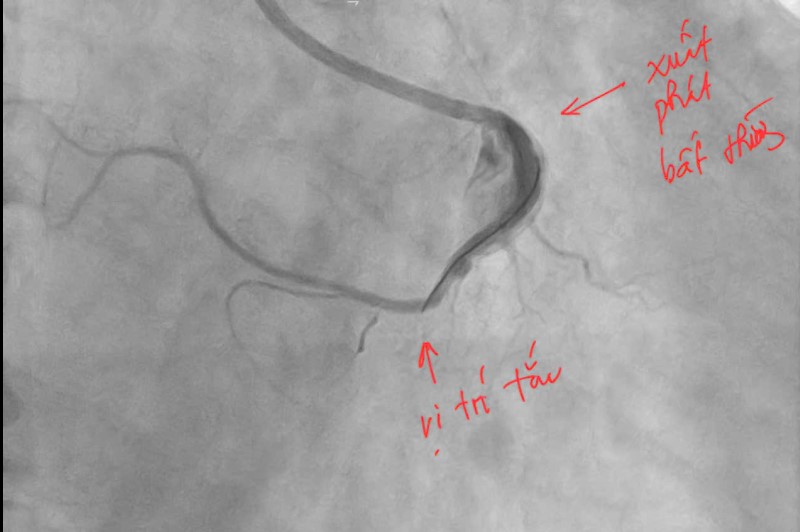

Đại diện Bệnh viện Bãi Cháy (Quảng Ninh) cho biết, mới đây các bác sĩ của đơn vị kịp thời cứu sống bệnh nhân nhồi máu cơ tim cấp trong tình trạng đặc biệt hiếm gặp. Đáng chú ý, động mạch vành phải của người bệnh xuất phát bất thường từ bên trái và xuất hiện biến chứng trong quá trình can thiệp mạch vành.

Hình ảnh trước khi can thiệp.

Ngay lập tức, bệnh nhân được kích hoạt quy trình cấp cứu tim mạch và chuyển đến phòng can thiệp mạch vành khẩn cấp. Kết quả chụp mạch vành cho thấy, bệnh nhân bị tắc hoàn toàn động mạch vành phải đoạn 2. Đáng chú ý, động mạch vành phải của người bệnh có vị trí xuất phát bất thường từ xoang vành trái của động mạch chủ – một dạng dị dạng hiếm gặp khiến việc tiếp cận và can thiệp trở nên phức tạp hơn nhiều so với các trường hợp thông thường.